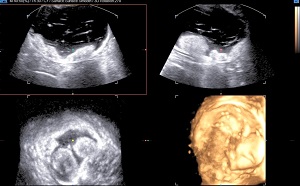

• Dermoid Cyst: Dermoid cyst in ovary is usually a benign tumor arising from totipotent germ cells. It may contain structures like hair, fluid, skin glands, teeth, etc. On sonography its echo texture is varying due to different contents within it.

Predominantly cystic mass with internal echoes and small well defined solid components.

Complex mass with cystic and solid components. Solid component cast acoustic shadowing suggestive of presence of bone/tooth within it.

Complex dermoid cyst with larger solid component.